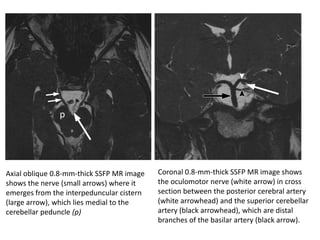

Trochlear nerves (arrows) where they

emerge from the dorsal midbrain to cross

the ambient cisterns. The characteristic

course of the trochlear nerves allows their

differentiation from the nearby superior

cerebellar artery (arrowheads).

Trochlear nerves (arrows)where they emerge from the dorsal midbrain to cross the ambient cisterns. The characteristic course of the trochlear nerves allows their differentiation from the nearby superior cerebellar artery (arrowheads).